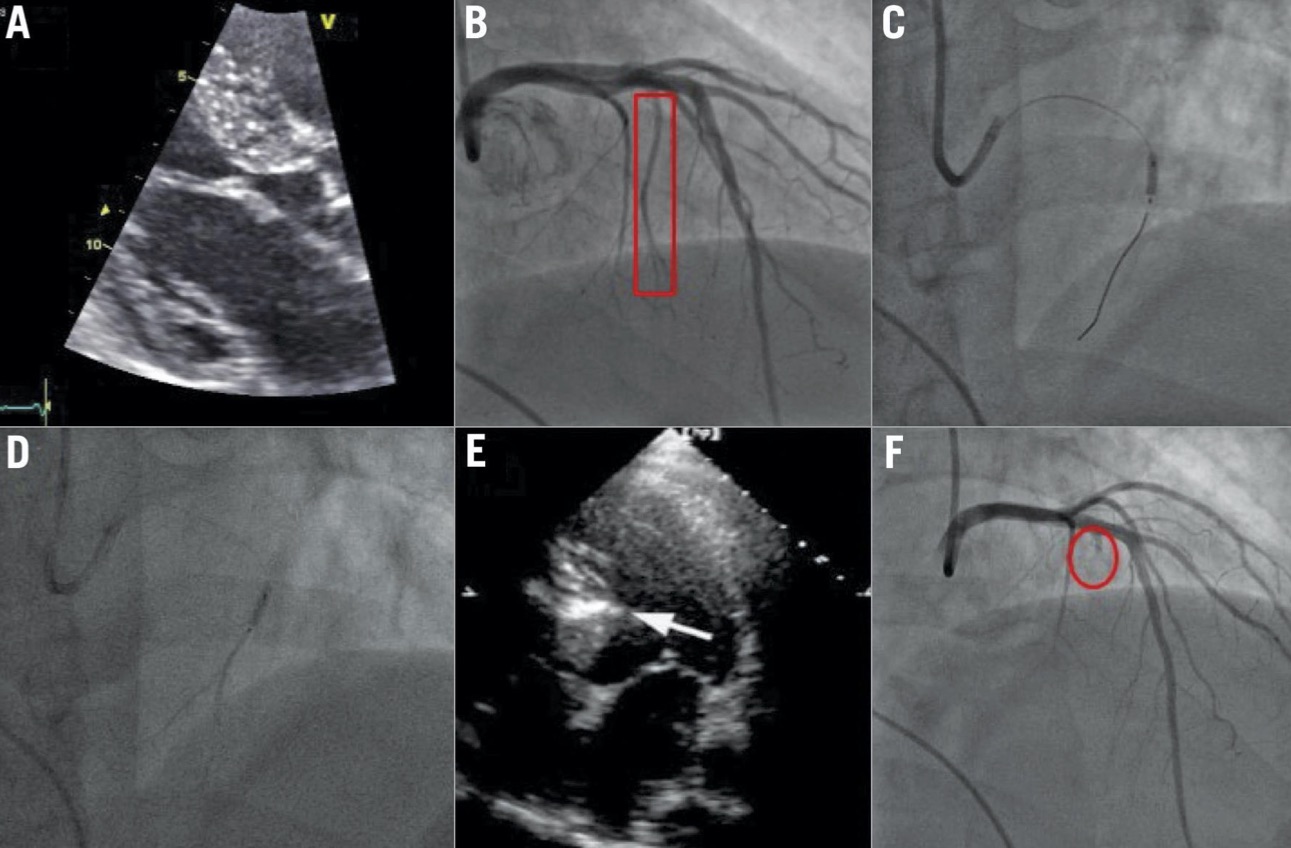

- Mediante coronarografia si individua il ramo dell’arteria coronarica sinistra che irrora la zona del setto interventricolare che ostruisce l’efflusso del ventricolo sinistro (ramo settale).

- Mediante Ecocardiografia con mezzo di contrasto si conferma che la zona dove giungerà l’alcool iniettato nel ramo settale corrisponde alla zona del setto interventricolare ipertrofico responsabile dell’ostruzione.

Immagini – Alcoolizzazione settale percutanea